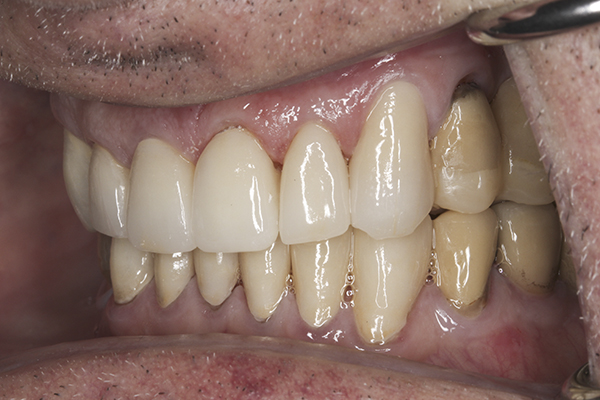

(11.) Preoperative left lateral, closed view.

Figure 11